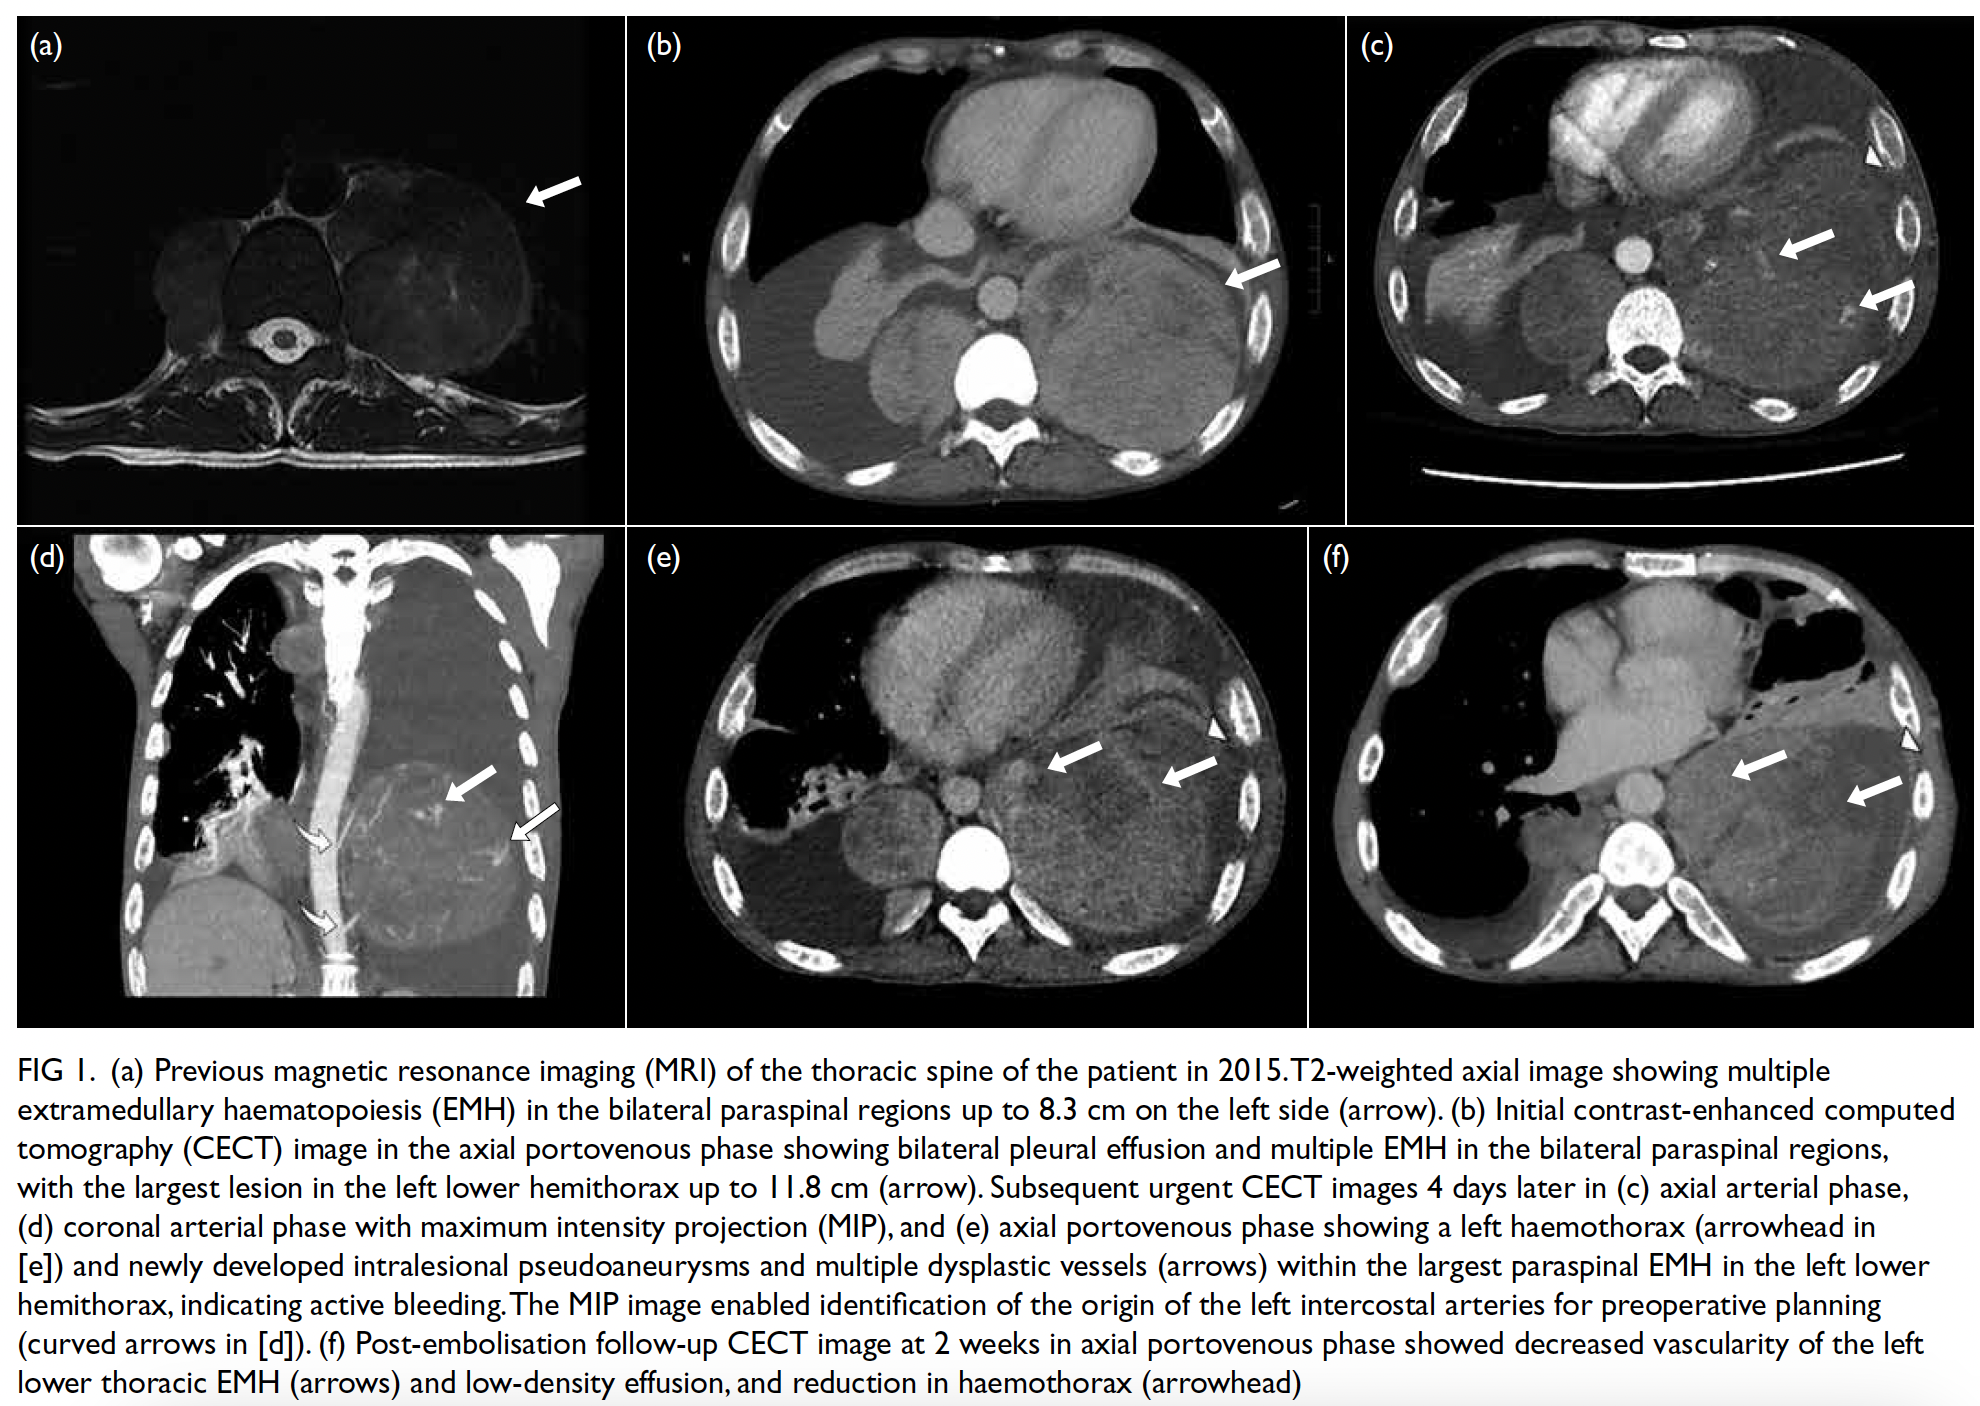

He had multiple extramedullary haematopoietic

(EMH) lesions in the bilateral paraspinal regions,

evident on previous magnetic resonance imaging (Fig 1a). Following a recent viral infection in January

(Fig 1b).

Figure 1. (a) Previous magnetic resonance imaging (MRI) of the thoracic spine of the patient in 2015. T2-weighted axial image showing multiple extramedullary haematopoiesis (EMH) in the bilateral paraspinal regions up to 8.3 cm on the left side (arrow). (b) Initial contrast-enhanced computed tomography (CECT) image in the axial portovenous phase showing bilateral pleural effusion and multiple EMH in the bilateral paraspinal regions, with the largest lesion in the left lower hemithorax up to 11.8 cm (arrow). Subsequent urgent CECT images 4 days later in (c) axial arterial phase, (d) coronal arterial phase with maximum intensity projection (MIP), and (e) axial portovenous phase showing a left haemothorax (arrowhead in [e]) and newly developed intralesional pseudoaneurysms and multiple dysplastic vessels (arrows) within the largest paraspinal EMH in the left lower hemithorax, indicating active bleeding.The MIP image enabled identification of the origin of the left intercostal arteries for preoperative planning (curved arrows in [d]). (f) Post-embolisation follow-up CECT image at 2 weeks in axial portovenous phase showed decreased vascularity of the left lower thoracic EMH (arrows) and low-density effusion, and reduction in haemothorax (arrowhead)

A few days later, the patient developed sudden

chest pain, with tachycardia and hypotension (blood

pressure: 82/43 mm Hg). Urgent CT of the thorax

revealed a left haemothorax and blood products

adjacent to the largest paraspinal EMH in the left

lower hemithorax, along with new intralesional

pseudoaneurysms and multiple dysplastic vessels,

indicative of active bleeding (Fig 1c-e). A left chest

drain was placed, yielding 1.3 L of heavily blood-stained

fluid. He was referred to interventional

radiologists for urgent embolisation to control the

bleeding.

Follow-up CT 2 weeks later showed a reduction in

the left haemothorax and decreased vascularity of

the left lower thoracic EMH (Fig 1f). The patient was

discharged and remains asymptomatic to date, with

no clinical evidence of re-bleeding.